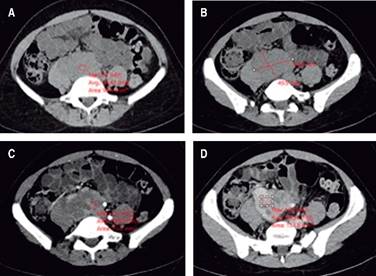

Se trata de paciente femenina de 35 años sin antecedentes personales patológicos de importancia; refiere iniciar su padecimiento actual en junio del 2020 con dolor importante en espalda baja, tolerable sin atenuantes ni agravantes, tratado con manejo conservador presentando mejoría parcial de la sintomatología. Meses después se incrementó la sintomatología, siendo el dolor más intenso y frecuente en el mismo sitio, además de irradiarse hacia ambas caderas y piernas. Acude a consulta para protocolo de estudio. Se solicitaron tomografía axial computarizada de abdomen en fase simple y con contraste endovenoso. Se identificó una lesión ocupante de espacio que se localiza en el retroperitoneo, infrarrenal, por delante y paramedial derecha de los cuerpos vertebrales L4 a S1; es de contornos lobulados, delimitada posterior y hacia la derecha por el músculo psoas y por los cuerpos vertebrales, los cuales se observan íntegros; ocasiona desplazamiento hacia ventral de la vena cava inferior y medial y hacia posterior de la vena iliaca derecha, desplaza hacia la izquierda las arterias iliacas primitivas. Su densidad promedio es de 45 UH en la fase simple y con el contraste endovenoso presenta reforzamiento heterogéneo con incremento del índice de hasta 79 UH en la fase arterial y de hasta 98 UH en la fase venosa y persiste con similares índices en la fase tardía de eliminación. Compromete el tránsito de contraste de la vena iliaca derecha y de la porción proximal de la vena cava inferior, las cuales no se logran distinguir, mientras que la vena iliaca izquierda muestra franco incremento en su diámetros y retorno lento del contraste. La lesión mide 62 mm en transverso, hasta 57 mm en diámetro anteroposterior y 49.9 mm en cefalocaudal (Figuras 1 y 2).

Figura 1: A y B) Tomografía computada del abdomen en cortes simples a la altura de L5, lesión sólida retroperitoneal entre el músculo psoas y los grandes vasos del retroperitoneo. C y D) Cortes con contraste endovenoso en fases arterial y venosa, reforzamiento heterogéneo, desplaza las venas iliacas internas.